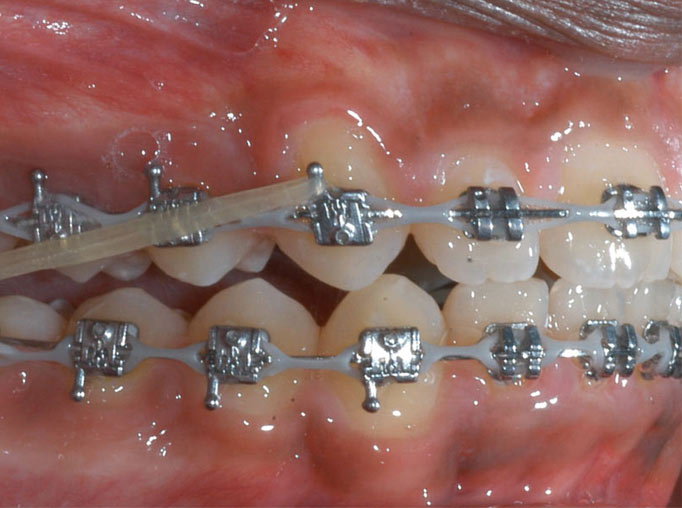

大多数前牙开颌患者都接受矫正来治疗,前牙开颌是一种牙齿畸形,影响外貌美观,影响口腔功能,终影响人的身体健康,前牙开颌通过矫正的方法恢复过来。那么前牙开颌矫正效果怎么样?下文为大家揭晓一下。

前牙开颌矫正

前牙开颌矫正

前牙开颌矫正效果怎么样?矫正越早,效果越好

前牙开颌矫正是无年龄限制的,不过通常情况下女孩子在10到12岁期间进行牙齿矫正较好,男孩子在11到13岁进行牙齿矫正较好。因为这个时期,人的面部发育仍处于生长发育的快速期,而牙齿矫正就是需要利用面部生长发育的潜力,以确保牙齿移动及牙槽骨改建的效率达到较佳状态,从而取得完美的矫正效果。